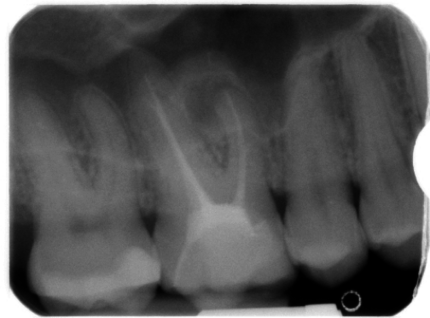

„Videoübertragung der ersten Live-Demonstration einer endodontischen Revisionstherapie an der Akademie: Entfernung der alten Wurzelfüllmaterialien“

Damals zwar bereits ein etabliertes Verfahren, jedoch mit einigen technischen Schwierigkeiten behaftet. So wurden während der Demonstration mehrere Methoden der Entfernung von Guttapercha aus den Wurzelkanälen gezeigt, die von der Handinstrumentation über die 360°-rotierende maschinelle Präparation bis hin zum thermoplastischen Erweichen von Guttapercha reichten. In der zweiten Live-Demonstration wurde dann beim gleichen Behandlungsfall vier Wochen später die laterale kalte Verdichtung von Guttapercha als Wurzelfülltechnik demonstriert. In der Bildergalerie zum Beitrag finden sich die dazugehörigen Röntgenaufnahmen.